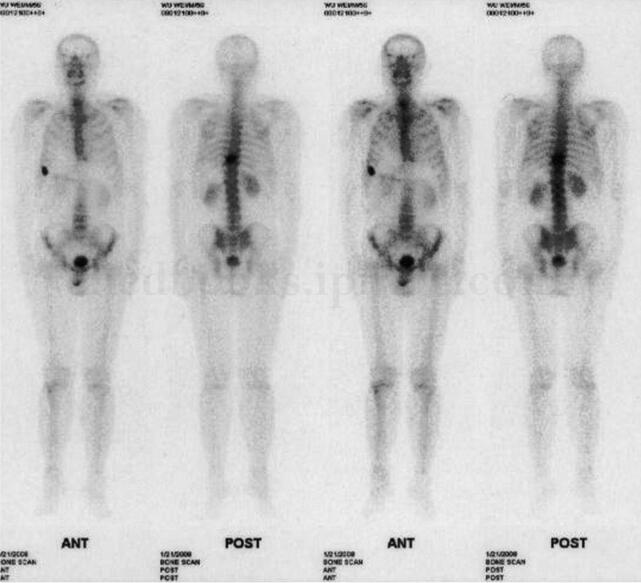

患者,男,57岁,主因肝癌术后1年,胸背部疼痛2个月,门诊入院。患者1年前于外院诊断为肝癌,行肝左叶切除,2个月前无明显诱因出现胸背部疼痛,当地医院检查全身骨扫描显示右第7 前肋及第9 胸椎放射性异常浓集,为进一步诊治门诊入院。

图21‐1 全身骨扫描示右第7 前肋及第9 胸椎放射性异常浓集

影像学检查:全身骨扫描示右侧第7 前肋及第9 胸椎放射性异常浓集,骨骼其余部位未见转移性病灶(图21‐1)。CT 示第9 胸椎体溶骨性破坏,局部可见软组织肿块。MRI 示第9胸椎体骨质破坏,软组织肿块形成并向右后方突出,相应水平椎管狭窄,胸髓受压变形,与肿物分界不清,增强扫描后见肿物强化明显且不均匀(图21‐2)。